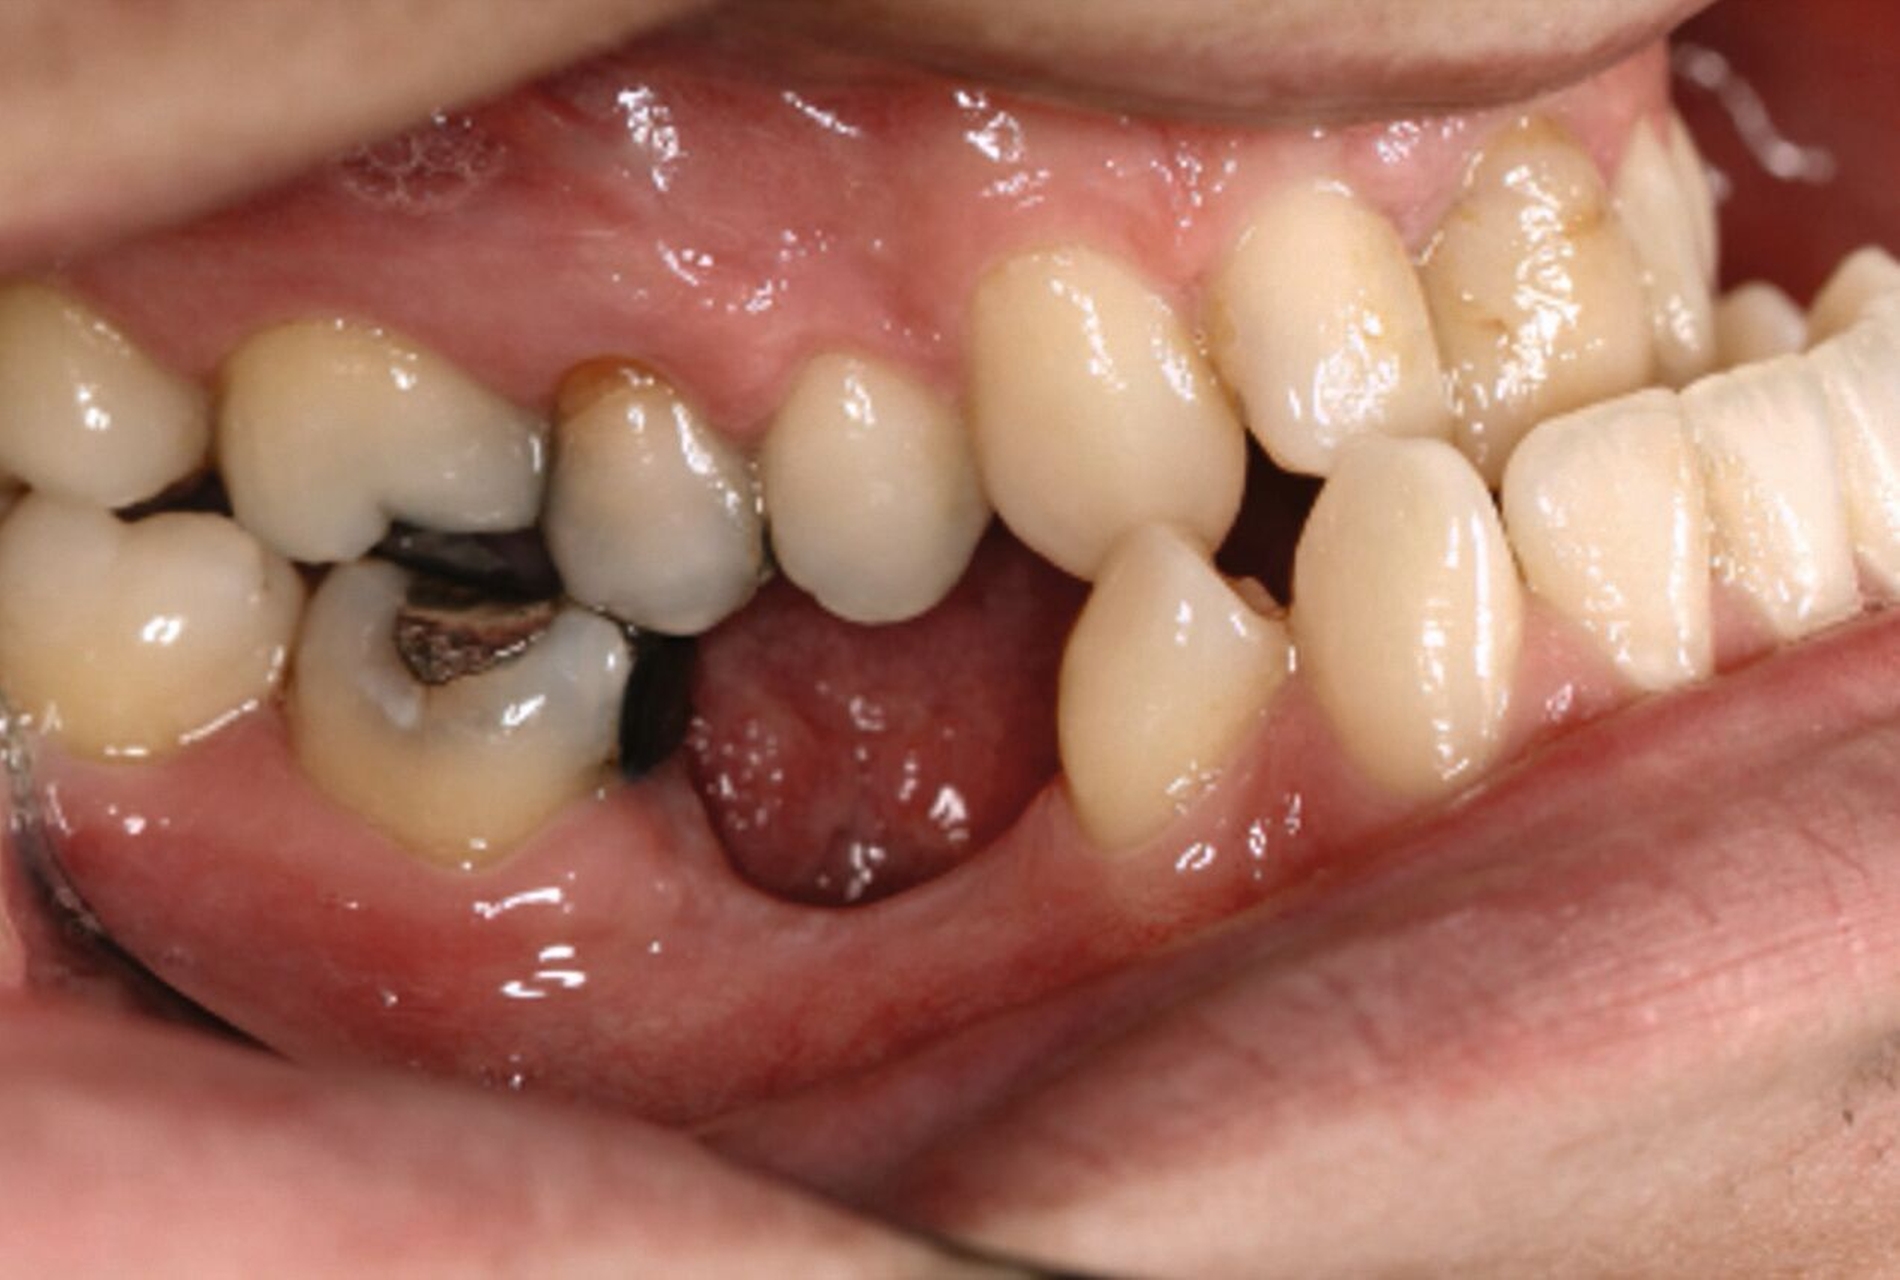

Ein 25-jähriger Patient stellte sich mit dem Wunsch nach Optimierung seines Erscheinungsbildes und seiner Kaufunktion in der kieferorthopädischen Praxis vor (Abbildung 1). Klinisch zeigten sich eine Angle-Klasse-III-Verzahnung mit einer 3/4 Prämolarenbreite Mesialokklusion beidseits und ein zirkulärer Kreuzbiss von 18–12/48–41 und 21–28/31–37. Es lagen ein negativer Overjet von -6,7 mm und ein Overbite von 5,1 mm vor. Eine Mittellinienverschiebung wurde sowohl im Oberkiefer – mit einer Abweichung von 4 mm nach rechts – als auch im Unterkiefer – mit einer Abweichung von 3 mm nach links – diagnostiziert (Abbildungen 2 und 3).

Aufgrund einer hohen Kariesanfälligkeit und einer klinisch floriden Parodontitis waren bereits mehrere Zähne des Patienten extrahiert worden, darunter 16, 11, 25, 38, 35, 45 und 46. Die mesiale Kippung und Aufwanderung der angrenzenden Zähne ließ vermuten, dass der Zahnverlust zeitlich weiter zurücklag. Aufgrund der reduzierten Langzeitprognose des Zahnes 11 entschieden wir uns gemeinsam mit dem Patienten für eine Ausgleichsextraktion des Frontzahns.